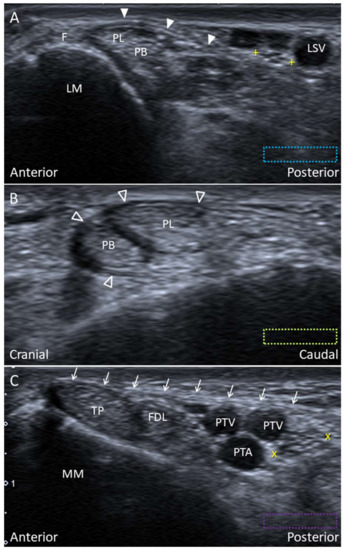

4.1.1. Anatomy

4.1.2. Scanning Technique

4.1.3. Clinical Relevance

4.3.1. Anatomy

4.3.2. Scanning Technique

4.3.3. Clinical Relevance

4.4.1. Anatomy

4.4.2. Scanning Technique

4.4.3. Clinical Relevance